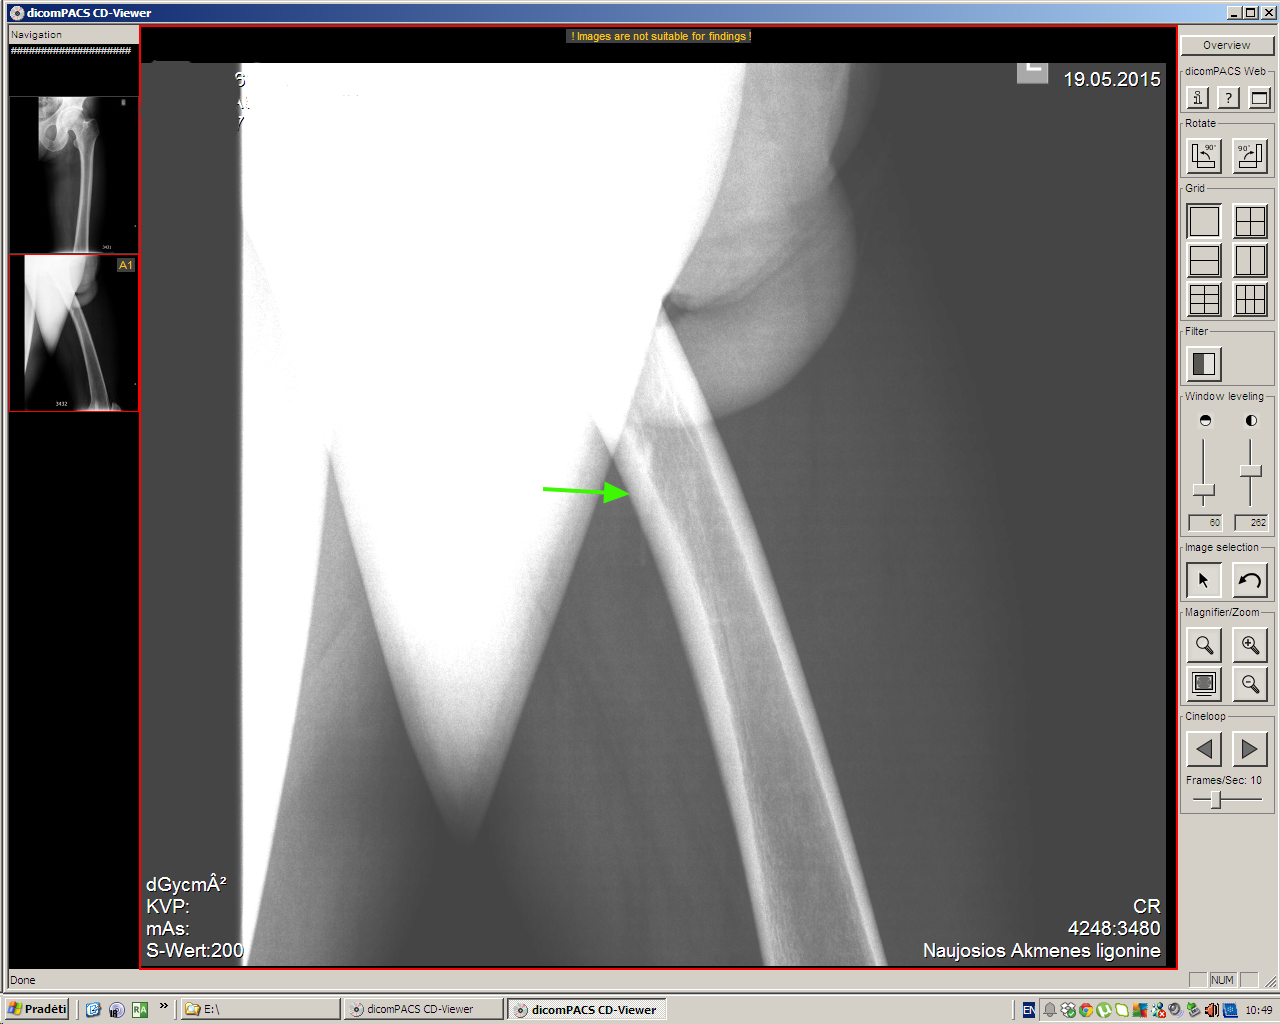

Молодой мужчина, деревенский житель, обратился к доктору по поводу образования на передней поверхности бедра, тот отправил на рентген (патологии не обнаружено), а затем УЗИ.

Ультразвуковое исследование здесь было более информативным, чем обычный рентген, хотя если присмотреться, то и на рентгеновском снимке шип можно увидеть.